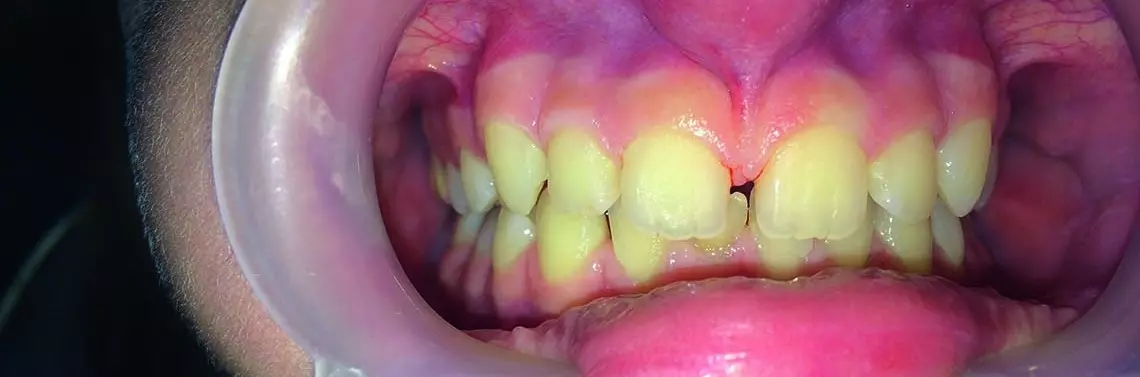

Wędzidełko wargi górnej – frenulektomia

Wędzidełko jest zbudowane z tkanki łącznej włóknistej (włókna kolagenowe o różnej grubości), nabłonka warstwowego (z cechami orto- i parakeratozy), naczyń krwionośnych i limfatycznych, ponadto w niektórych przypadkach są obecne również gruczoły ślinowe, tkanka tłuszczowa, włókna sprężyste tkanki łącznej włóknistej, a nawet tkanka mięśniowa.

Typy wędzidełka

Ze względu na umiejscowienie przyczepu wędzidełka można wyróżnić jego następujące typy:

• typ I – śluzówkowy (błona śluzowa ruchoma),

• typ II – dziąsłowy (błona śluzowa wyrostka zębodołowego),

• typ III – brodawkowy (brodawka międzyzębowa),

• typ IV – penetrujący (brodawka przysieczna).

Typy brodawkowy i penetrujący (III, IV) są uważane za ...